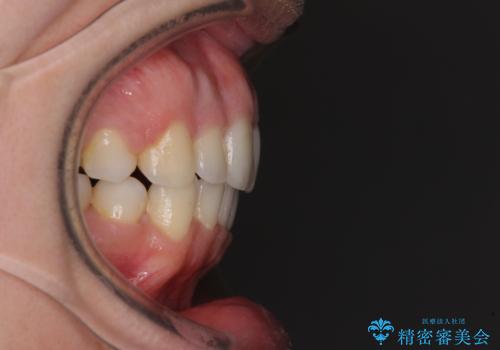

- 前歯のデコボコと口元の突出感を気にして来院された患者様です。

上下左右第一小臼歯4本を抜歯し、ワイヤー装置にて口元を引っ込めるよう矯正治療を行うこととしました。

叢生が強かったため、口元の突出感の改善には限界がありましたが、横側からも口元が引っ込んだ感じが分かるほど改善されました。